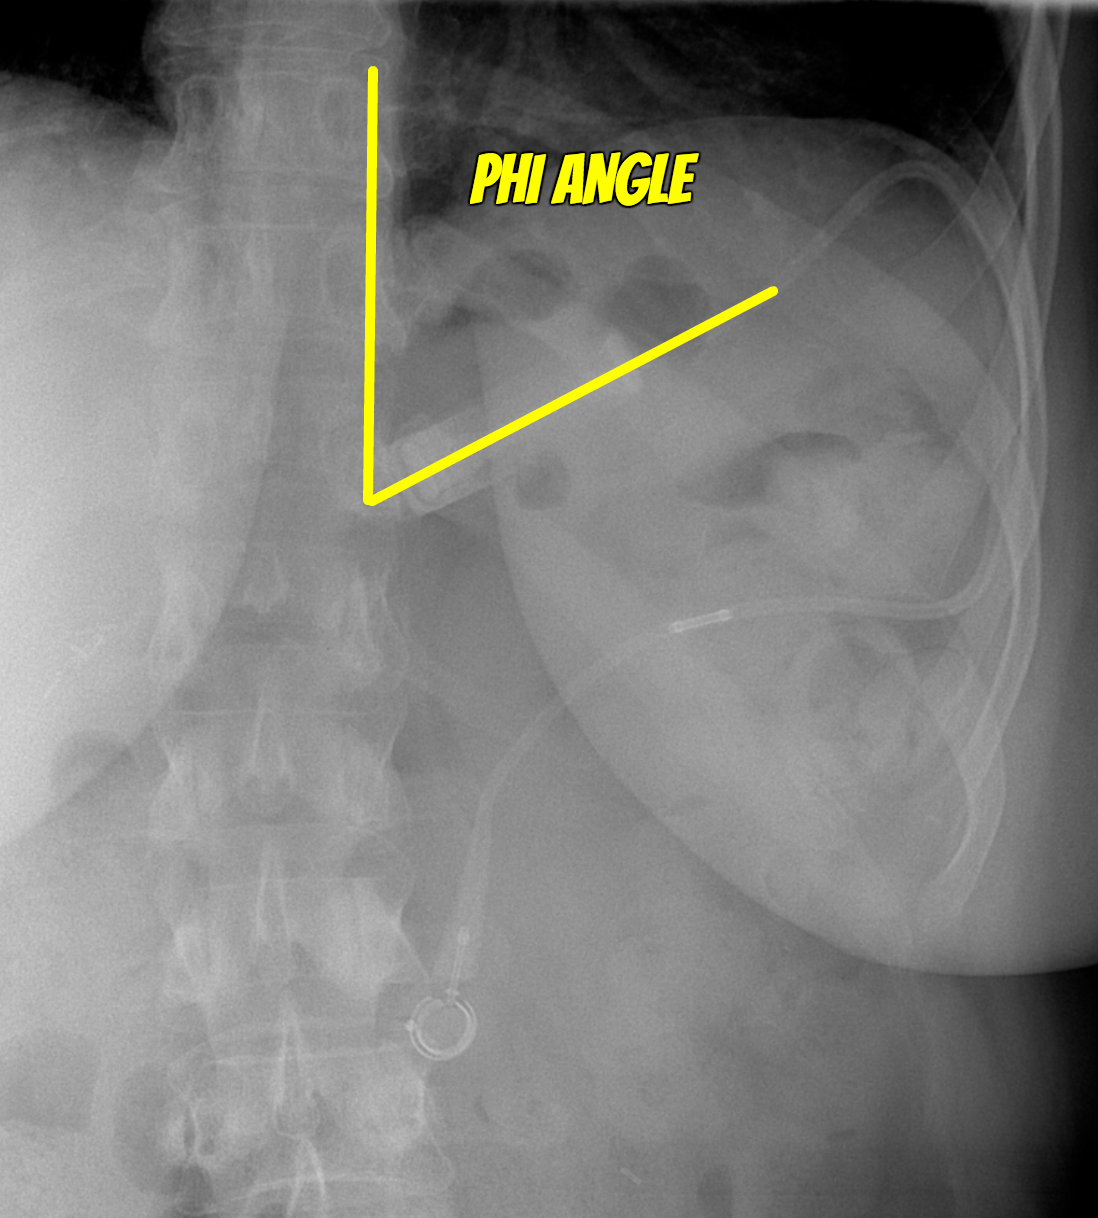

Phi Angle

• Angle formed between gastric lap band and spine

• Normal = 4-58 deg (just remember between 6-60 as it is easier to remember and its very unlikely you’ll be tested on a case of 59 or 5 degrees)

• If angle is greater than this it suggests compromised lap band

• If lap band is perpendicular to the spine = bad